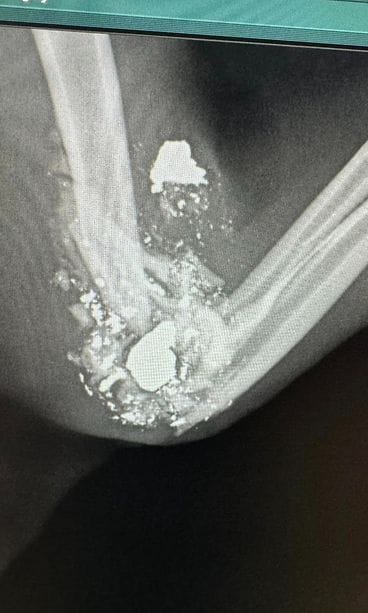

– Lääkäri huomasi, että Kimmon jalka on pahasti rikki. Jalasta otettiin röntgenkuva. Kun kuva aukesi, niin lääkäri totesi, että tätä kissaahan on ammuttu. Osa jalasta on tohjona. Kuvassa näkyi myös kaksi kissaan kuulumatonta kappaletta, jotka olivat lääkärin mielestä luodin osia, Tolonen kertoo.